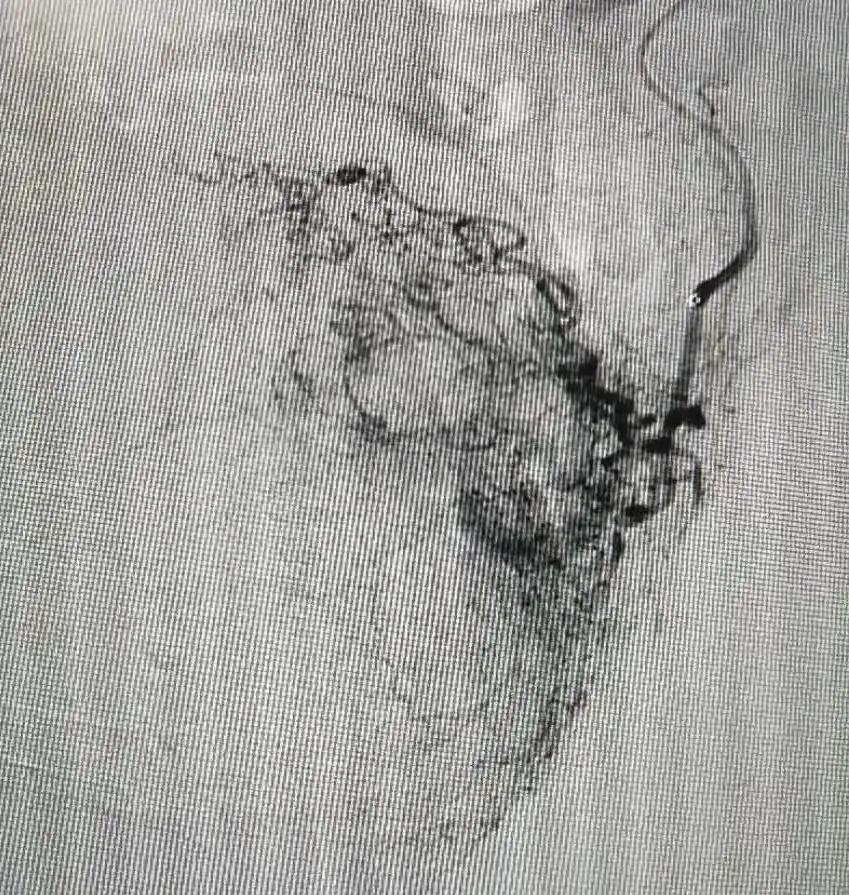

DSA下造影,找到肿瘤供血血管、可见肿瘤形态、大小。

手术方案:将化疗药直接通过导管注入到肿瘤内,之后用栓塞颗粒栓塞血管,遏制肿瘤供血血管。